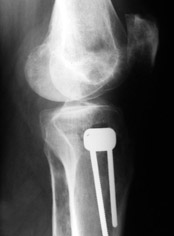

Картинки - в приложении.Будут вопросы - готов ответить.

Ещё картинка - схема. Хотя у Соломина всё написано.

Отправитель: T. Derek V. Cooke 13 Сентябрь 2005, 23:51

|

Hello Alex:

Thanks for the clinical photo.

Your patient appears to have "Insquinting Knees"?

I am attaching a word doc with a 'print screen' of the program in use, showing the images being viewed and analysed

. On the right leg you can see some of the tools (from the tool bar above) applied to demonstrate a mild mech-axis varus of about 5 degrees.

On the left the bone landmarks used in the anlaysis are shown.

The data for the analysis are in the XLs sheet below, exported from the program automatically.

I have given a label of the abreviations and some normative values.

In essence she has a mild mech-axis varus of 7 degrees with some contribution from the femur (2) degrees and more from the tibia (6 degrees), none from the joint.

The analysis took about 6 mins.

Regards

Derek